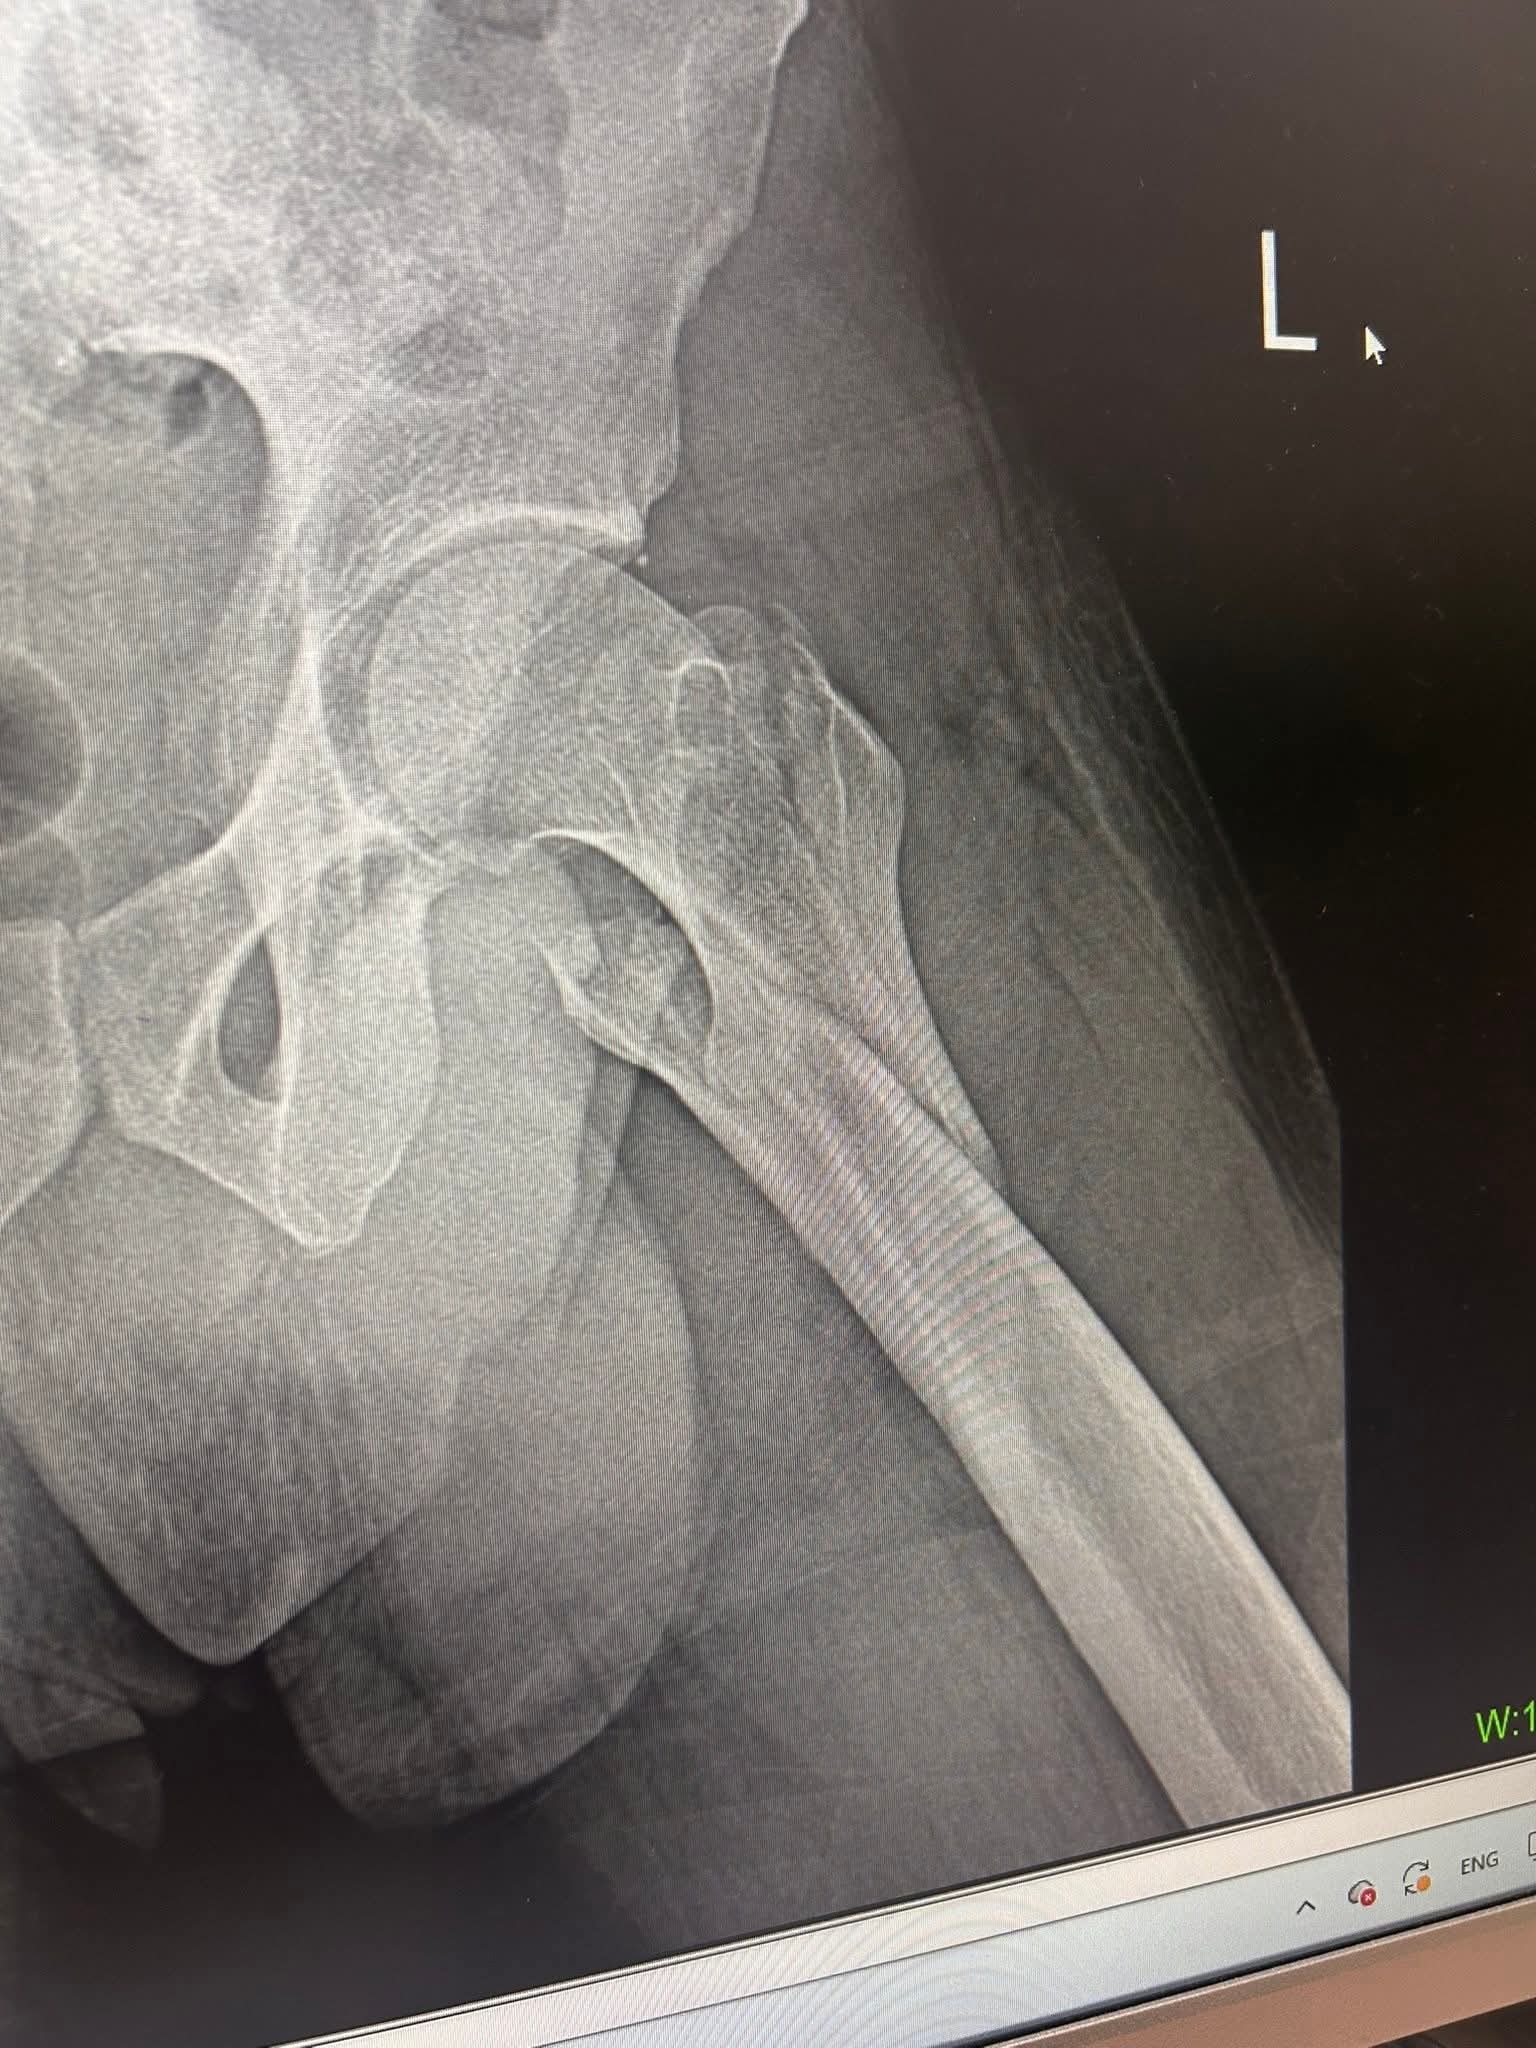

Krisstian P. Jurado—beloved friend, protector, and genuinely good human from Hermiston, Oregon—is facing the kind of nightmare no one expects while traveling abroad. While visiting Chiang Mai, Thailand, Krisstian stepped in to protect his friend Charlie during a violent attack and robbery outside a club. In doing what he’s always done—showing up for others—Krisstian was seriously injured. He suffered a badly broken femur, a broken nose, and the group lost a significant amount of cash during the assault.

Krisstian is currently hospitalized at Chiang Mai Ram Hospital, far from home, family, and any familiar support system. He is facing major surgery on his femur and a long, painful recovery. Unfortunately, his U.S. health insurance is not accepted in Thailand, and the hospital has already quoted a substantial cost for surgery alone. Additional expenses for his hospital stay, medications, and treatment for his other injuries are still unfolding. Once stabilized, Krisstian will need to return home to the United States. Depending on medical recommendations, this may require upgrading his plane seat to travel safely while in a cast or with limited mobility. There may also be unforeseen costs related to follow-up care or pursuing justice for what happened.